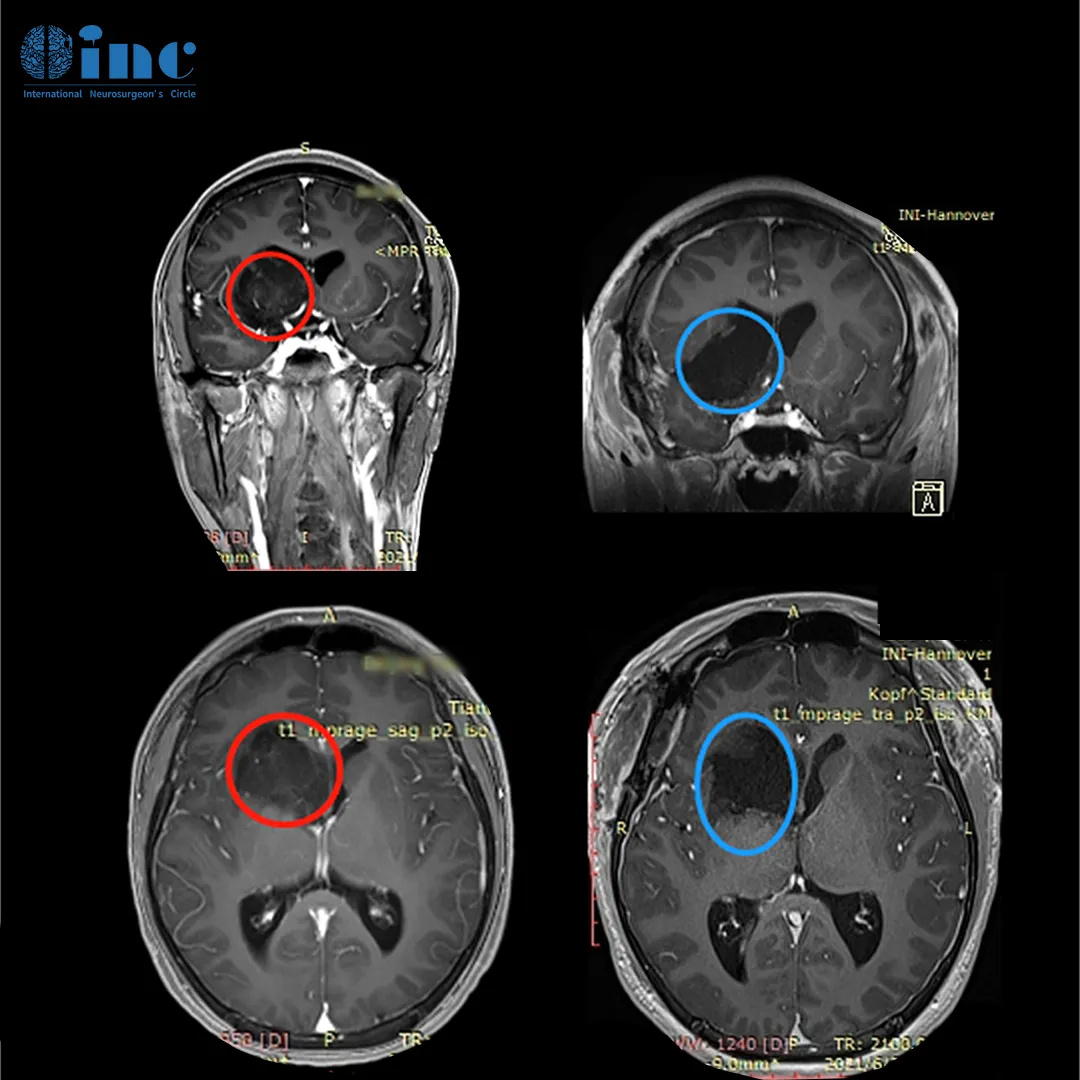

▼巴教授神经导航引导下切除基底神经节海绵状瘤。a,术前t1加权MR图像显示病变向内囊附近延伸。b,海绵状血管瘤瘤完全切除后的术后t2加权MRI

▼巴教授基底神经节海绵状血管瘤,54岁男性。该患者在神经导航的帮助下进行手术。A-C,术前MR图像显示右侧尾状核海绵状血管瘤。D,神经导航定位、皮肤切口等。E,海绵状血管瘤完全切除后的术后CT扫描。F,术后10天无神经功能缺损。

巴教授2023年6月中国行期间,一位68岁右侧基底节占位-海绵状血管瘤的柯女士通过INC咨询来到巴教授苏州独墅湖医院咨询室。因症状加重,病灶增大,问诊多名神经外科医生,两个专家团队医生给出了截然不同的意见:不赞成手术治疗,理由是年龄大,手术导致瘫痪失语的风险大。另外一个医生团队的意见是现在可以马上手术,但效果不确定。当咨询巴教授之后,得到了的评估。在手术决策上,巴教授偏向手术,在手术风险上,教授表示有把握。

“血管畸形有可能会变大,也有可能会变小!如果血管畸形变大出血多,内囊的区域主管我们手脚的运动,患者就可能出现偏瘫。经过影像的对比,75%支持手术,25%支持可以再观察。如果症状加重,就需要治疗。要是真的等到偏瘫了再手术,那偏瘫恢复的机率要比现在要小很多。当然这个血管畸形是可以很好的切除的。”

INC巴教授主刀手术后

术后核磁显示,海绵状血管瘤得到顺利全切,柯女士的状态也好,神采奕奕,和常人无异。术后2天巴教授查房时,已经可以下地走路。看到前来查房的巴教授,柯女士激动,亲切拥抱感谢巴教授,终于摆脱了危险的基底节海绵状血管瘤的她满怀感激得握住巴教授的手说道,“我要看看巴教授这双神奇的大手,这是上帝之手,巴教授感谢你!”